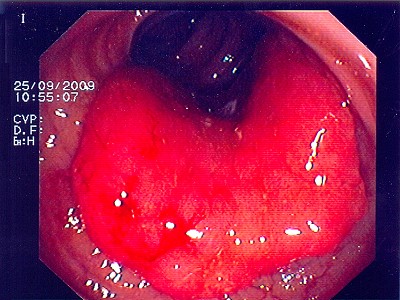

Abb. 1: Bösartiger Tumor des Übergangs von Mast- zu Dickdarm. Hier hilft ausschließlich eine Teilentfernung des Mast- und Dickdarmes. Abb. 1: Bösartiger Tumor des Übergangs von Mast- zu Dickdarm. Hier hilft ausschließlich eine Teilentfernung des Mast- und Dickdarmes.